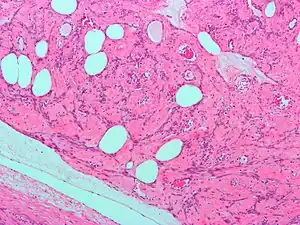

Histopathology of uterine fibroids typically show smooth muscle in a whorled (fascicular) pattern.[32]

Microscopically, tumor cells resemble normal cells (elongated, spindle-shaped, with a cigar-shaped nucleus) and form bundles with different directions (whorled). These cells are uniform in size and shape, with scarce mitoses. There are three benign variants: bizarre (atypical); cellular; and mitotically active.

Fibroids are a type of uterine leiomyoma. Fibroids grossly appear as round, well circumscribed (but not encapsulated), solid nodules that are white or tan, and show whorled appearance on histological section. The size varies, from microscopic to lesions of considerable size. Typically lesions the size of a grapefruit or bigger are felt by the patient herself through the abdominal wall.[1]